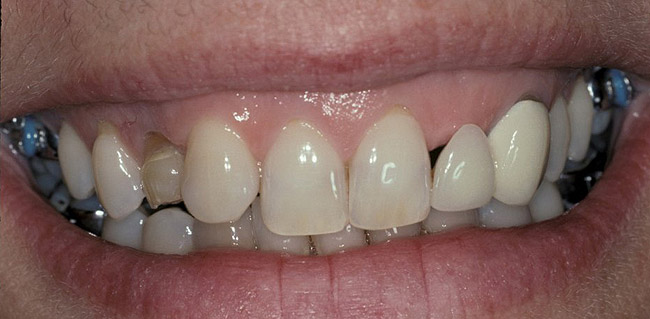

Figure 1  Initial presentation. Teeth Nos. 8 and 9 had internal and external resorption and were deemed hopeless. Recession of 4 mm was associated with tooth No. 9

Figure 1

Figure 5  A naturally low smile line hid the clinical “black triangle” from view.

Figure 5